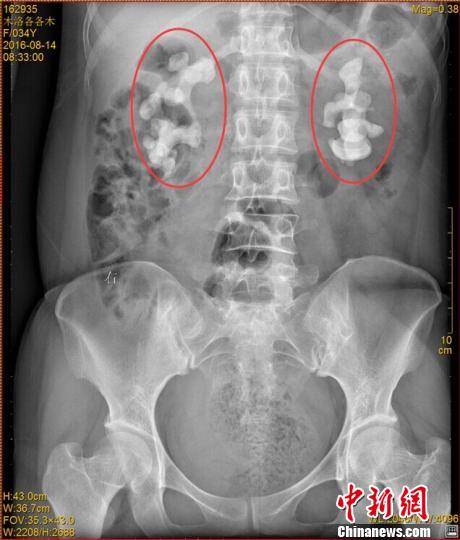

各各木術前影像圖片,紅圈內為巨大腎結石。 鐘欣 攝

中新網成都11月7日電 (王鵬)記者7日從四川省結石病醫院獲悉,該醫院近日收治了一名罕見腎結石病人。來自四川涼山的34歲女子各各木,雙腎長出10厘米巨型結石,腎內空間幾乎全被結石填滿。

“臨床上,雙腎長巨大結石的患者一般都是中老年男性,女性較為少見,年輕女性更加罕見。”四川省結石病醫院常立高醫生詳細檢查后發現,該女子雙腎內空間幾乎被結石全部填滿。他詢問患者后判斷,該罕見病例的出現與女子常年喝生水有直接關系。

記者了解到,由于各各木腎臟內部幾乎全被結石填滿,常規的開放式手術并不適用。醫院目前已對其進行了4次難度頗高的微創手術,且在進一步觀察治療當中。